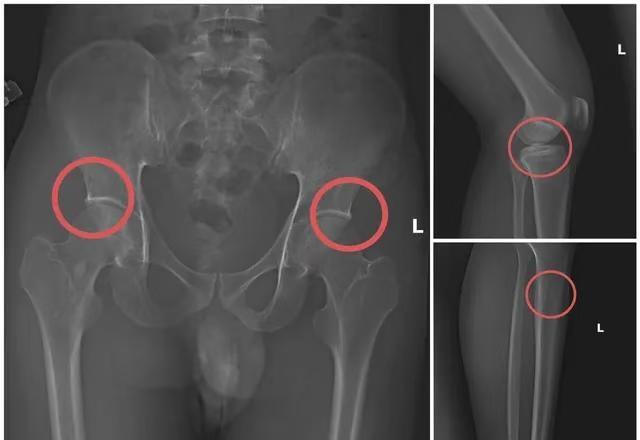

真狠!越南一伙人通过自残骗报,金额达60亿 这起案件太离谱、太残忍、太震撼了! 越南富寿省警方刚刚捣毁一个靠“自制骨折”骗保的犯罪团伙。 他们竟然为了钱,亲手把自己的骨头敲断!😱 🩻 案情曝光:为了骗保,他们真的“下狠手”了 这起诈骗案的主谋是 Ta Minh Chau(1995),曾是锦溪医疗中心员工。(图1) 多年医疗经验 + 骨骼结构知识 让他想出了一个极其残酷的骗保流程👇 🔧 “制造假骨折”的步骤是这样进行的—— • 直接给参与者注射麻醉剂 • 用注射器、锤子、钉子敲击骨骼 • 创造出与真实事故极为相似的裂缝和骨折 • 再指导受伤者伪造各种事故现场: ⚡“触电” 🤕“跌倒” 🌊“滑进溪流” 图2:受试者接受麻醉和骨科手术的区域现场 图3:X光片显示该物体造成的骨骼损伤 这些如此逼真的“意外”,让保险公司完全难以识破! 富寿省公安局长直言: “这种方法既残忍又不人道。” 参与者为了骗钱,把生命和身体当成可牺牲的“成本” 💰 他们骗了多少?数字惊呆所有人 这个团伙骗取多家大型寿险公司高额赔付,包括: 宏利、友邦、第一生命、富卫、永明、丘博人寿等… 📌 总金额超过 60 亿越南盾!(约 174 万人民币) 其中仅宏利一家公司就被骗走 26 亿越盾。 🧑‍⚕️ 参案人员众多 除了主谋 Châu,警方还紧急拘捕了: Hoàng Văn Trường、Hoàng Văn Thắng、Hoàng Thị Hồng Điệp、Nguyễn Anh Dũng 等多人。 这些人都在他的指使下: • 购买高额保险 • 接受“人为制造的伤情” • 提交理赔申请 • 分赃获利 🚓富寿省警方: ⚠️ 已对多名嫌疑人下达紧急逮捕令 ⚠️ 已临时拘留 6 名相关人员 ⚠️ 案件正在继续扩大调查 警方表示,这是一场 “系统化、专业化、医学知识深度介入的骗保工程”。 热点新闻事件 真实案件 坚决打击犯罪 越南新闻 正义永远不会缺席